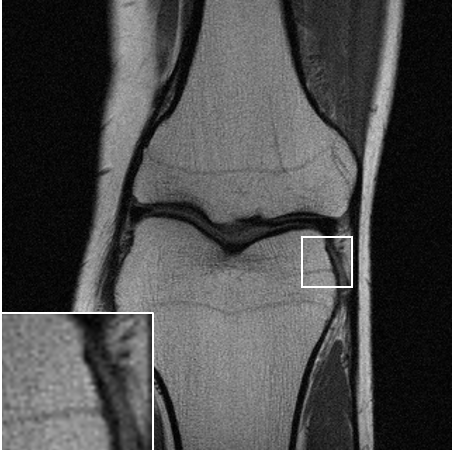

Table LABEL:tab:quant_results summarizes the results for the various experimental settings, comparing the performance of the above-mentioned benchmarks to ours. When compared to TV [6], our method achives an improvement of dB-dB in the peak-signal-to-noise ratio (PSNR). Similar results are observed for the structural-similarity measure (SSIM, about points improvement). As expected, the supervised model outperforms the proposed SSL method. However, it seems that at least for the lower distortion rates, this gap is surprisingly small. A visual inspection of the results over one slice is provided in Fig. 3. As can be observed in the zoomed-in region, our method manages to restore finer details better than the TV-based method, and even approaches the restoration levels of the supervised model in the lower distortion rates. As evident both quantitatively and visually, the TV-based method completely fails on the dealiasing task, whereas our SSL method seems to significantly alleviate the reconstruction artifacts.